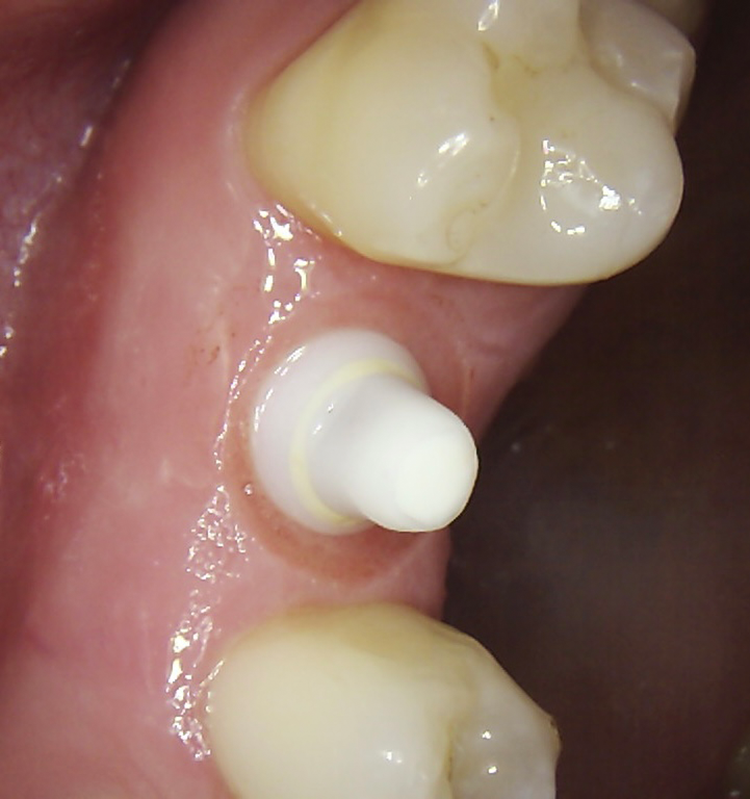

Bei dem balkonförmigen Implantat blieben die Alveolarkämme und der Kronenansatz erhalten (Abb. 4c und d). Der Spalt zwischen dem Implantat und der bukkalen Lamelle wurde mit A-PRF und einem Kollagenblock aufgefüllt, so dass keine zusätzliche Knochenaugmentation erforderlich war. Zusätzlich wurden PRF-Matrizen um, über, unter und neben dem Implantat im Knochen-Implantat-Raum positioniert (Abb. 1 bis 4b). Außerdem kam eine optionale Einheilscheibe (6 x 8 mm) zum Einsatz, um das Kollagen und die PRF zu sichern (Abb. 3b). Die Implantate zeigten bei einem Drehmoment von 35 Ncm Stabilität, welche mit dem Periotest-Gerät von Medizintechnik Gulden getestet wurde. Die Werte des Implantatstabilitätstests, die im Bereich von –8 bis 0 lagen, wurden als ideal für die Belastung angesehen (Tab. 3).

Die SDS-Zirkoniumdioxidimplantate wurden mit zementierten Pfosten weiter aufbereitet (Abb. 1d, 3 und 4c) und nach 4,74 + 0,95 Monaten Einheilzeit mit endgültigen Kronen versorgt. Die Balkonform ermöglichte ein natürliches Emergenzprofil, das die definitiven Kronen wie die Standardform ausrichtete sowie die Gesundheit des Weichgewebes und die Osseointegration förderte. Bei jeder Nachuntersuchung wurden Stabilität des Implantats, Zustand des umgebenden Gewebes und Vorhandensein von Zahnstein beurteilt.